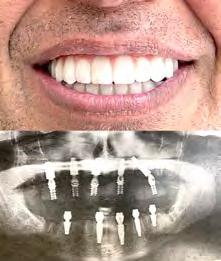

Лучшее качество услуг и материалов по разумной цене! Консультация и 3D снимок в подарок.

Установка одного импланта от

Одна из недавних операций:

Все-на-5-ти имплантах + несъемные зубы за 1 день

Высококлассные услуги по Зубной Имплантации в современной клинике, лимиторованной на установку имплантов.

* - установка 1 (одного) импланта не включая абатмент и коронку. Имплантация будет производится одним из специалистов клиники под руководством доктора Александра Антипова, челюстно-лицевого хирурга. Цена указана для пациентов, оплачивающих наличными.

(916) 827-3605

# 13 (2023) • 9 июля Газета «Диаспора» – все о нас с вами ПО ВОПРОСАМ РАЗМЕЩЕНИЯ РЕКЛАМЫ ОБРАЩАЙТЕСЬ ПО ТЕЛЕФОНУ: (916) 487-9701 или (916) 705-0739 10 Замещение всех зубов на 4-х, 6-ти имплантах Одиночные импланты Несколько имплантов ИМПЛАНТАЦИЯ ЗУБОВ

FREE Consultation and CT-Scan

911 Reserve Dr., Ste #150, Roseville, CA 95678 | Phone: (916) 827-3605

$998*